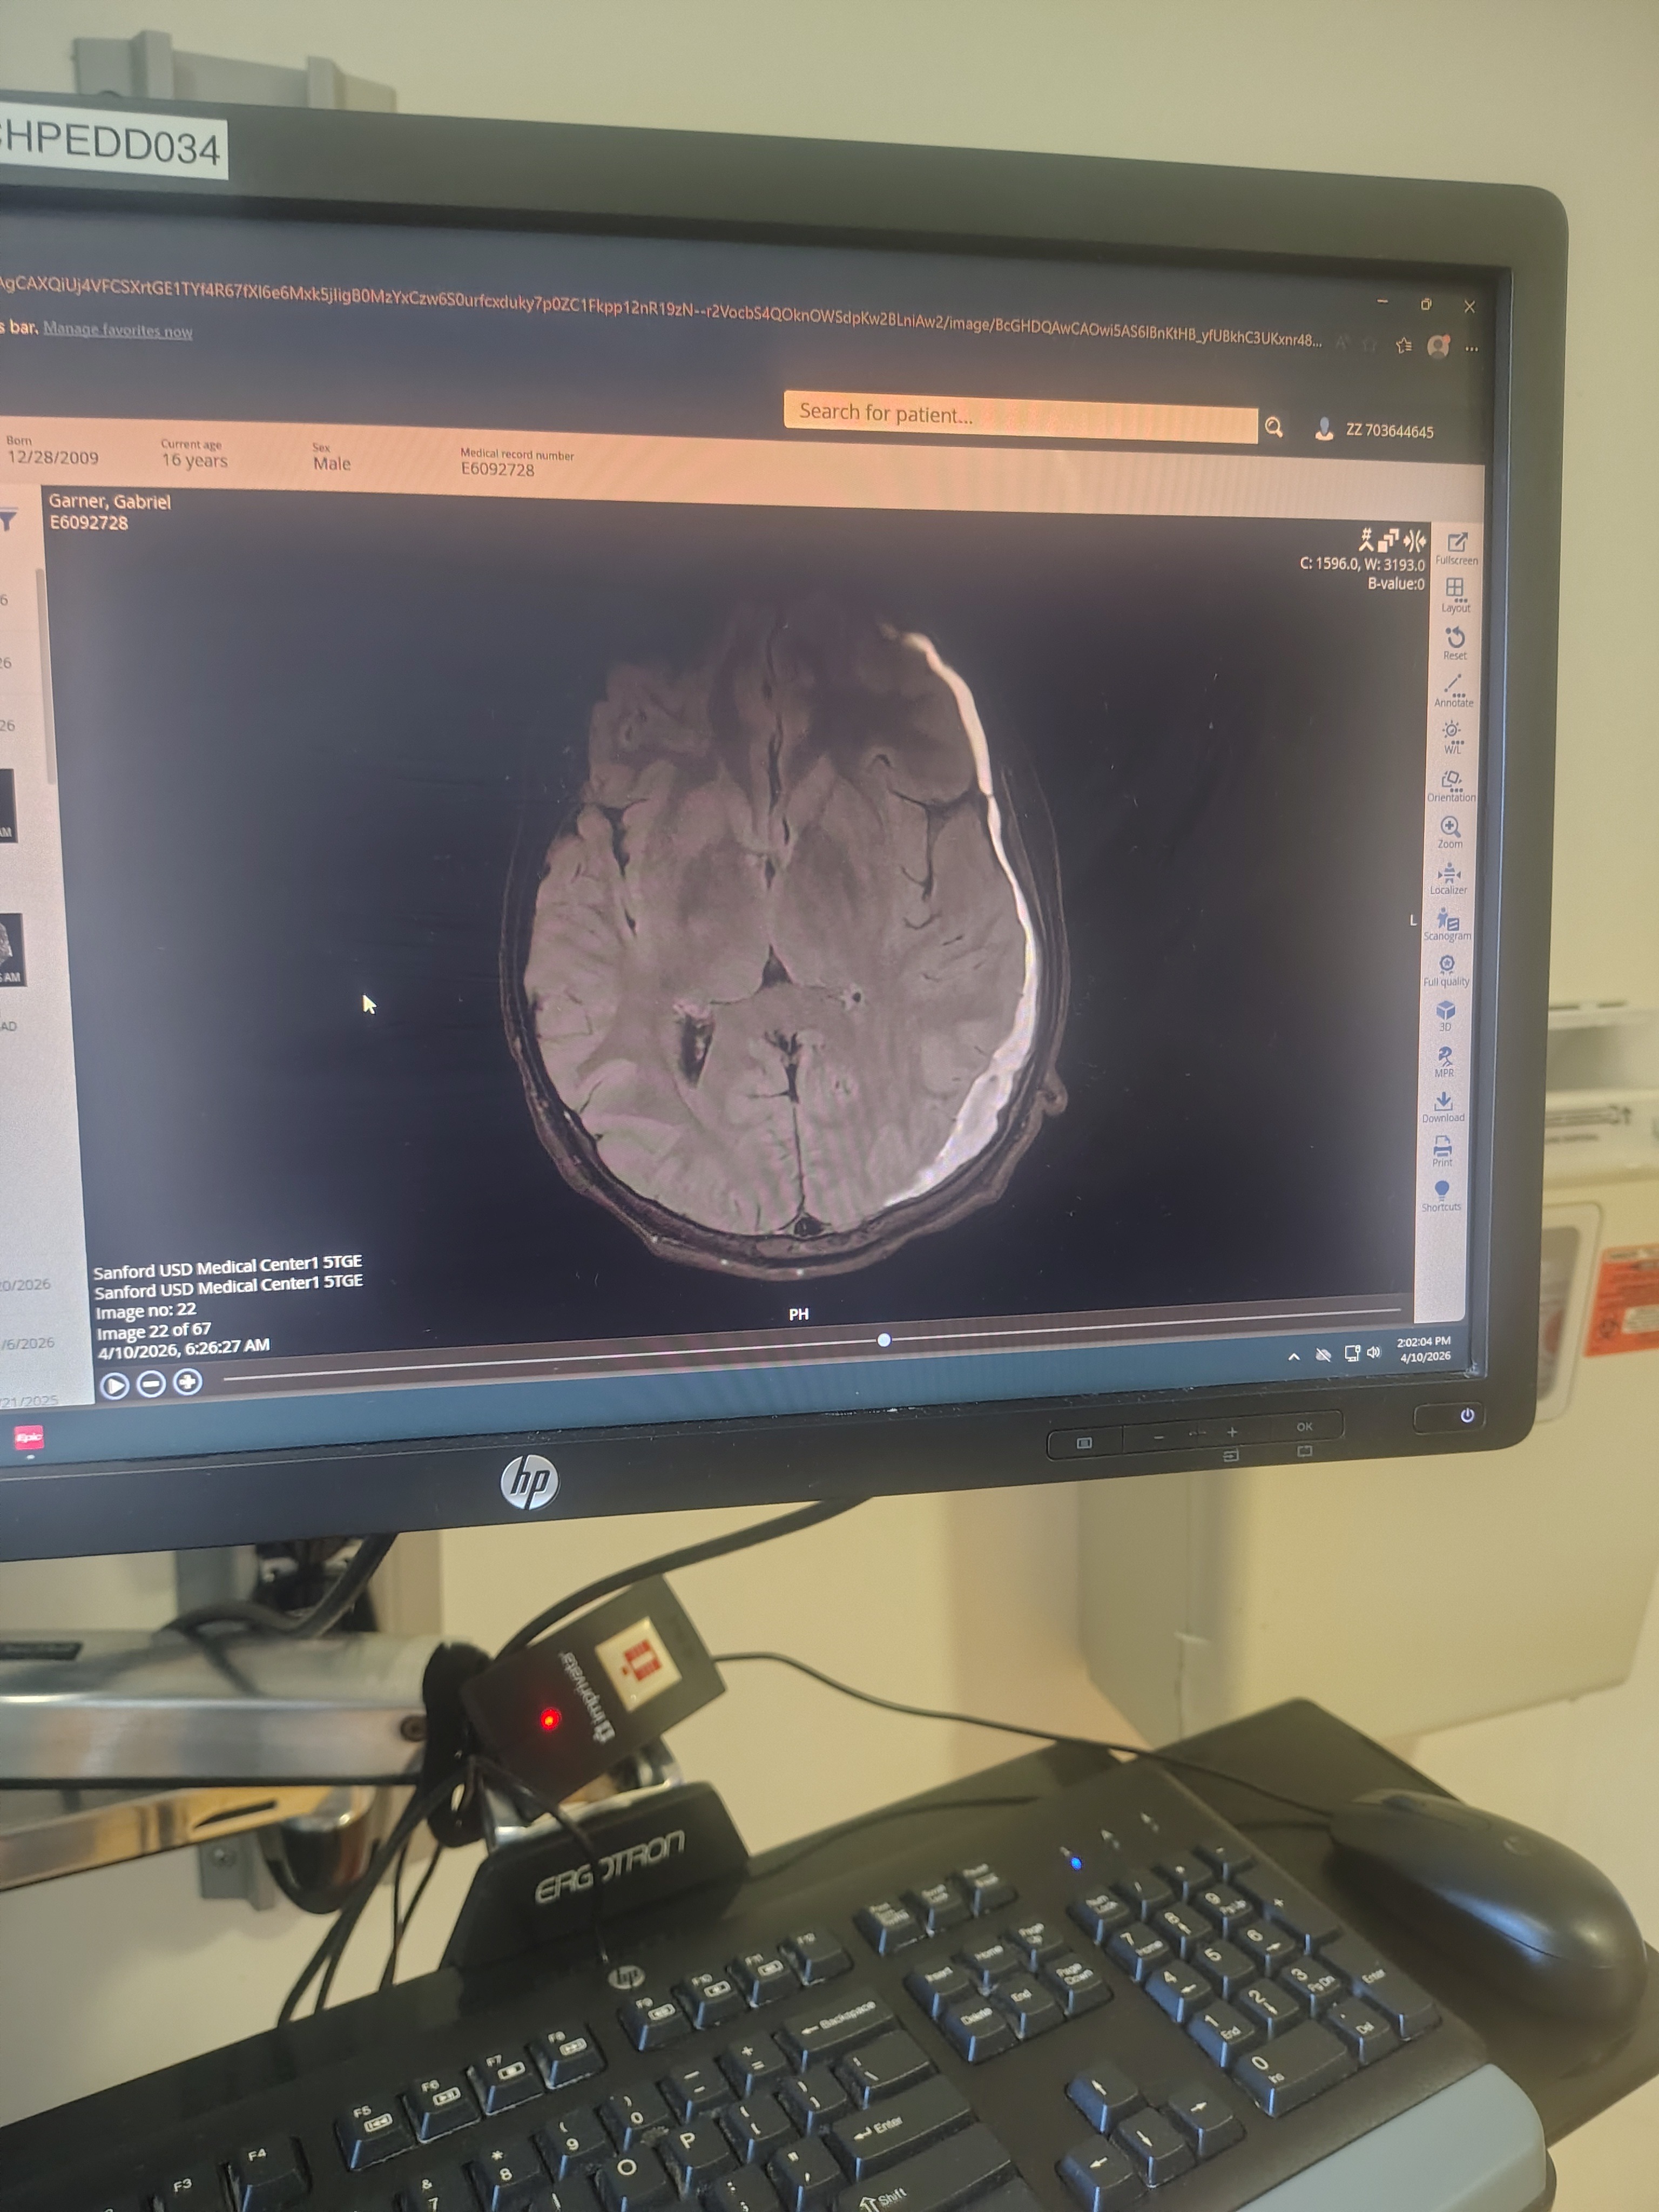

My son Noah has always been a fighter. He was born with Marfan Syndrome, a genetic condition that has brought many medical challenges into his life. Recently, we received the devastating news that Noah has developed five brain bleeds. This has turned our world upside down and required me to become his full-time caretaker, forcing me to step away from work to be by his side every day.